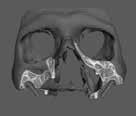

A modern diagnosztikai módszerek és a fejlett kezelési lehetőségek segítségével a fogászatban az endodontiai kezelések sikerességi aránya meredeken emelkedett az elmúlt évtizedekben. Ha az ortográd megközelítés nem szünteti meg az előforduló tüneteket, lege artis gyökércsatorna jelenlétében obturáció esetén az apex és a gyulladt periapikális szövetek sebészi eltávolítását alkalmazzák rutinbeavatkozásként. Az implantológiai fogászat újításai és a CBCT jelenléte egy olyan lehetőséget nyújthat, amely kombinált módszert kínál a lépések csökkentésére és a gyógyulás elősegítésére az apikoektómia után. Az egyedülálló CBCT és számos tervezőszoftver által biztosított egyedülálló vizualizáció javíthatja a tervezési fázist és a pontosságot bármilyen műtétnél. Ezek a módszerek széles körben elterjedtek az implantológiai fogászatban napjainkban. Ezért a cél ugyanaz, a 3D tervezés és a 3D nyomtatott sebészeti útmutatók a fogászat más területein is alkalmazhatók. Másrészről a gyökérvégműtét szükségessége bizonyos esetekben elkerülhetetlen. A dokumentáltan széles körű sikerek miatt a korai sebészeti endodontiai kezelések sikere (44-95%), az apikális sebészeti beavatkozások elveinek újratervezése a sebészeti mikroszkópok használatával releváns kérdés volt. A minimál invazív sebészeti terápiát Kim S. et al. vezette be és írta le alapmódszerként és azóta megkezdődött a fogászati sebészet forradalma. Ez inspirált minket arra, hogy megtaláljuk és bizonyítsuk ezt az újszerű módszert, amely 3D nyomtatott sablonokat és trepint kombinál az apikoektómiához. A előadás először a célzott endodontiai mikrosebészet területén elért legújabb innovációkat tekinti át, kezdve a terület 2007-es első preklinikai kutatásától. Szó lesz a technika fejlődéséről, valamint azokról az innovatív lépésekről, amelyek a jelenleg hangsúlyozott, teljesen irányított endodontiai műtéthez vezettek egy trepinnel, de. A vonatkozó preklinikai és klinikai kísérletek is bemutatásra kerülnek, bemutatva a technikának a hátterét, amelyet mára már számos esettanulmányban ismertettek, de csak néhány valós tudományos tanulmányban.

Ötvenes éveiben járó hölgyet fogorvosa irányította hozzánk a bal alsó 4-es fogának nagy méretű reszorpciójával [9. kép]. A hölgy ragaszkodott foga megmentéséhez, így a kezelés megtervezéséhez CBCT felvételt készítettünk a fogról [10. kép]. A felvételen a Patel-féle klasszifikáció szerinti Patel 3Ap reszorpciós elváltozás látható. A szájüregi vizsgálat során a fog bukkális felszínén gyulladt ínyt, mély parodontális tasakot és a fog nyaki részén, a foganyagon átsejlő reszorpciós lacunát találtunk [11. kép]. A fog szenzibilitás vizsgálat során nem reagált hideg ingerlésre. A pulpális érintettség miatt elvégeztük a fog trepanálását, majd lebenyt alakítottunk a kavitás láthatóvá tételéhez [12.

1. és 2. kép: Külső nyaki reszorpciós elváltozások CBCT képen.9. kép: Referáló orvos által készített röntgenfelvétel – 10. kép: CBCT felvételen 3 dimenzióban értékelhető a reszorpciós kavitás kiterjedése.